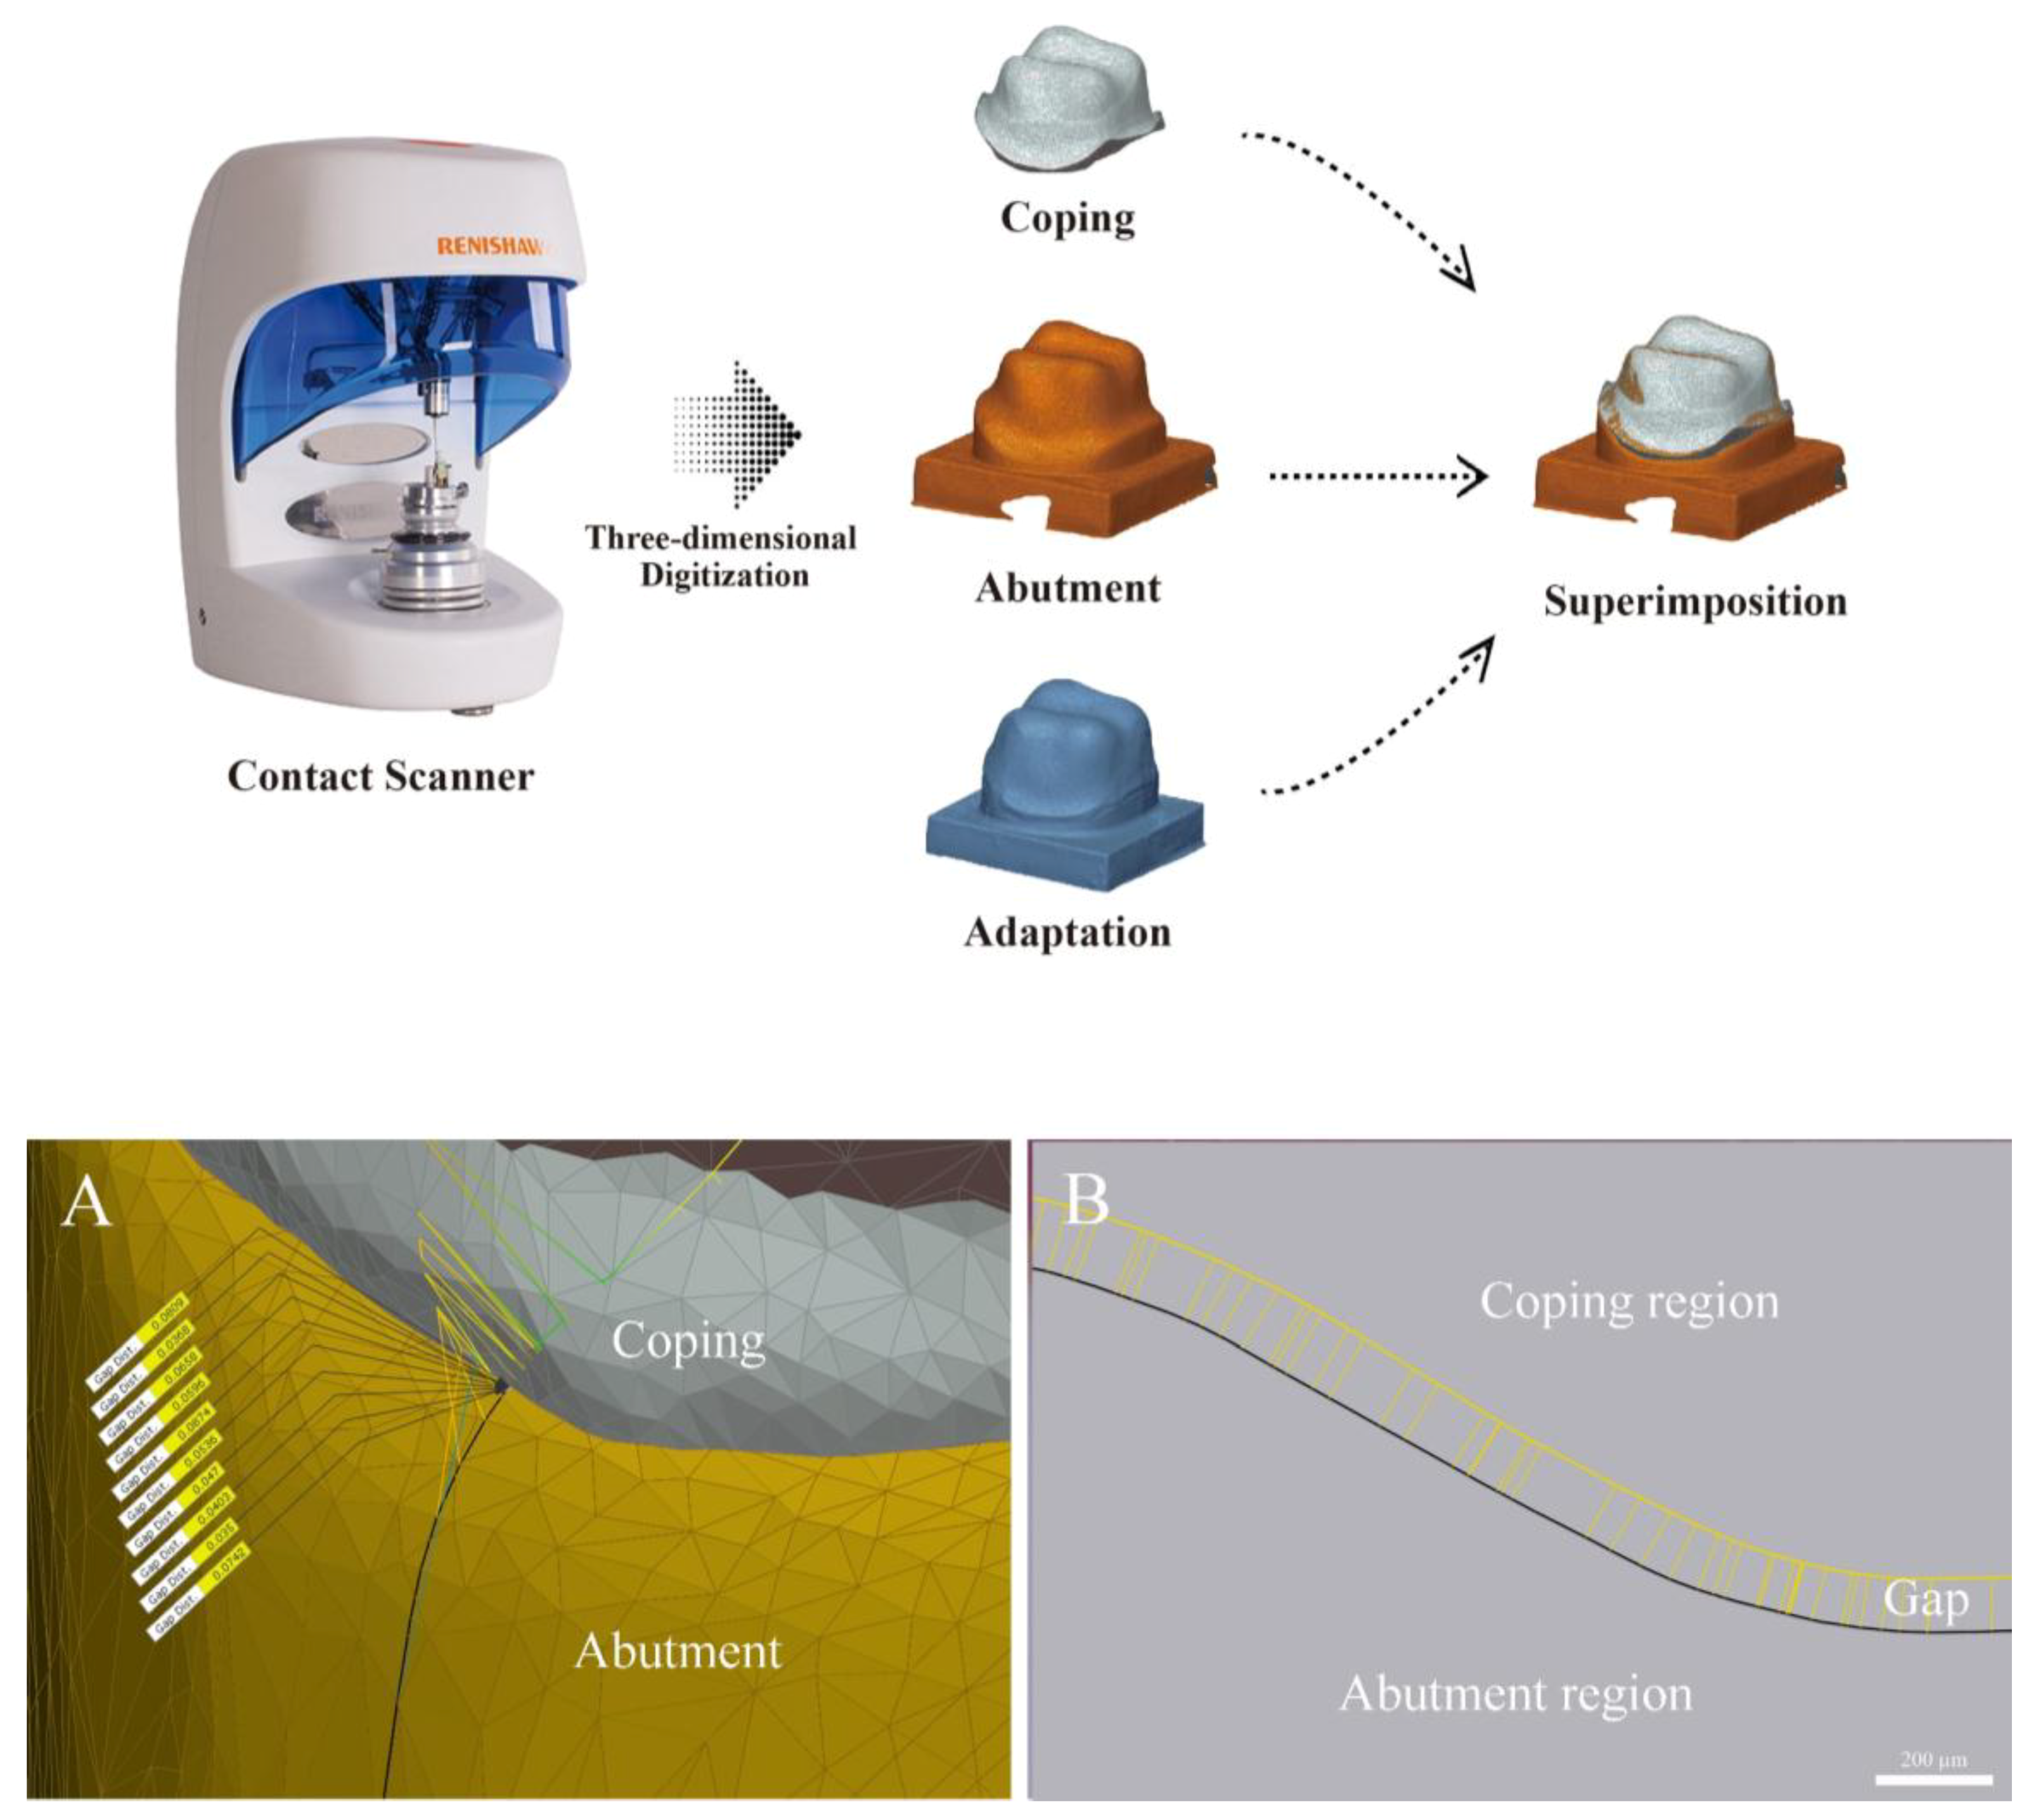

- The silicone replica technique (SRT): SRT is performed using the same protocol as cementation of a prosthesis. However, the method involves injecting silicone instead of cement inside the prosthesis and duplicating the internal and marginal fit for measurement. Since this is a relatively simple, low-cost method allowing the measurements to be made directly in the oral cavity, it has been utilized in many studies [21,22,23,24,25,26,30]. However, there is a possibility of deformation and tearing of the impression materials [31,32,33,34]. Additionally, CSM and SRT can make assessments only using two-dimensional (2D) analysis.

2.2.2. Silicone Replica Technique (SRT Group)